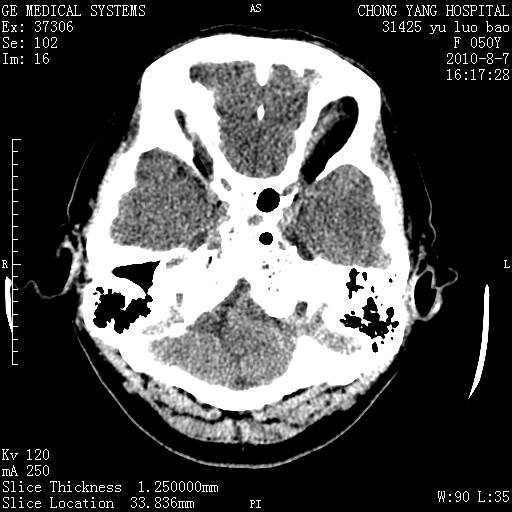

标题: CT28285:听力下降一年,头昏。 [打印本页]

标题: CT28285:听力下降一年,头昏。

右侧桥小脑角区占位--听神经瘤,建议增强或mri检查。

右侧桥小脑角去等密度占位,右侧内听道扩大、骨质吸收,考虑:右侧听神经瘤,建议增强检查。

右侧内听道扩大、骨质吸收,中脑受压左移,考虑:右侧听神经瘤,建议增强检查。支持!

右侧桥小脑角区等密度占位,内耳道扩大,听神经瘤